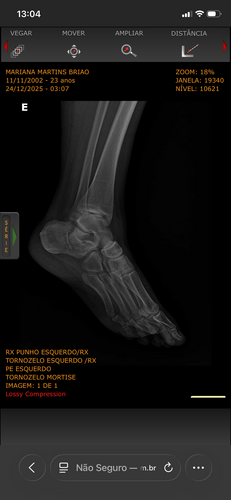

Eu acabei quebrando o calcanhar e o braço, vou precisar passar por duas cirurgias para colocar placas e ficarei uns meses sem poder me locomover e trabalhar infelizmente.